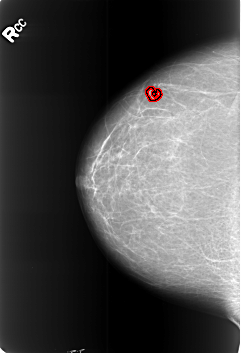

B_3451_1.RIGHT_CC

RIGHT_CC LINES 5648 PIXELS_PER_LINE 3856 BITS_PER_PIXEL 12 RESOLUTION 50 OVERLAY

FILE: B_3451_1.RIGHT_CC.OVERLAY

TOTAL_ABNORMALITIES 1

ABNORMALITY 1

LESION_TYPE MASS SHAPE LYMPH_NODE MARGINS N/A

ASSESSMENT 2

SUBTLETY 3

PATHOLOGY BENIGN_WITHOUT_CALLBACK

TOTAL_OUTLINES 1

BOUNDARY